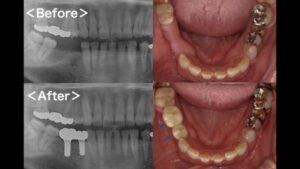

骨が少ない人には骨再生治療で対応

インプラント治療に必要な条件として、顎の骨の厚みがあります。顎の骨が薄いとうまくインプラントを植立できず、治療が困難になるのです。その場合は次のような骨再生療法を行い、“インプラント治療が可能な土台”を整えます。

GBR

骨が不足している箇所に膜で骨を作るスペースを確保し、その中に骨の素となる物質を注入して骨の再生を促します。

サイナスリフト

頬の骨の中は大きな空洞になっており、その部分を「サイナス(上顎洞)」といいます。サイナスを覆う粘膜を持ち上げて上顎の骨との間にすき間を作り、そこに骨の素になる物質を注入し、骨が作られるのを待ちます。